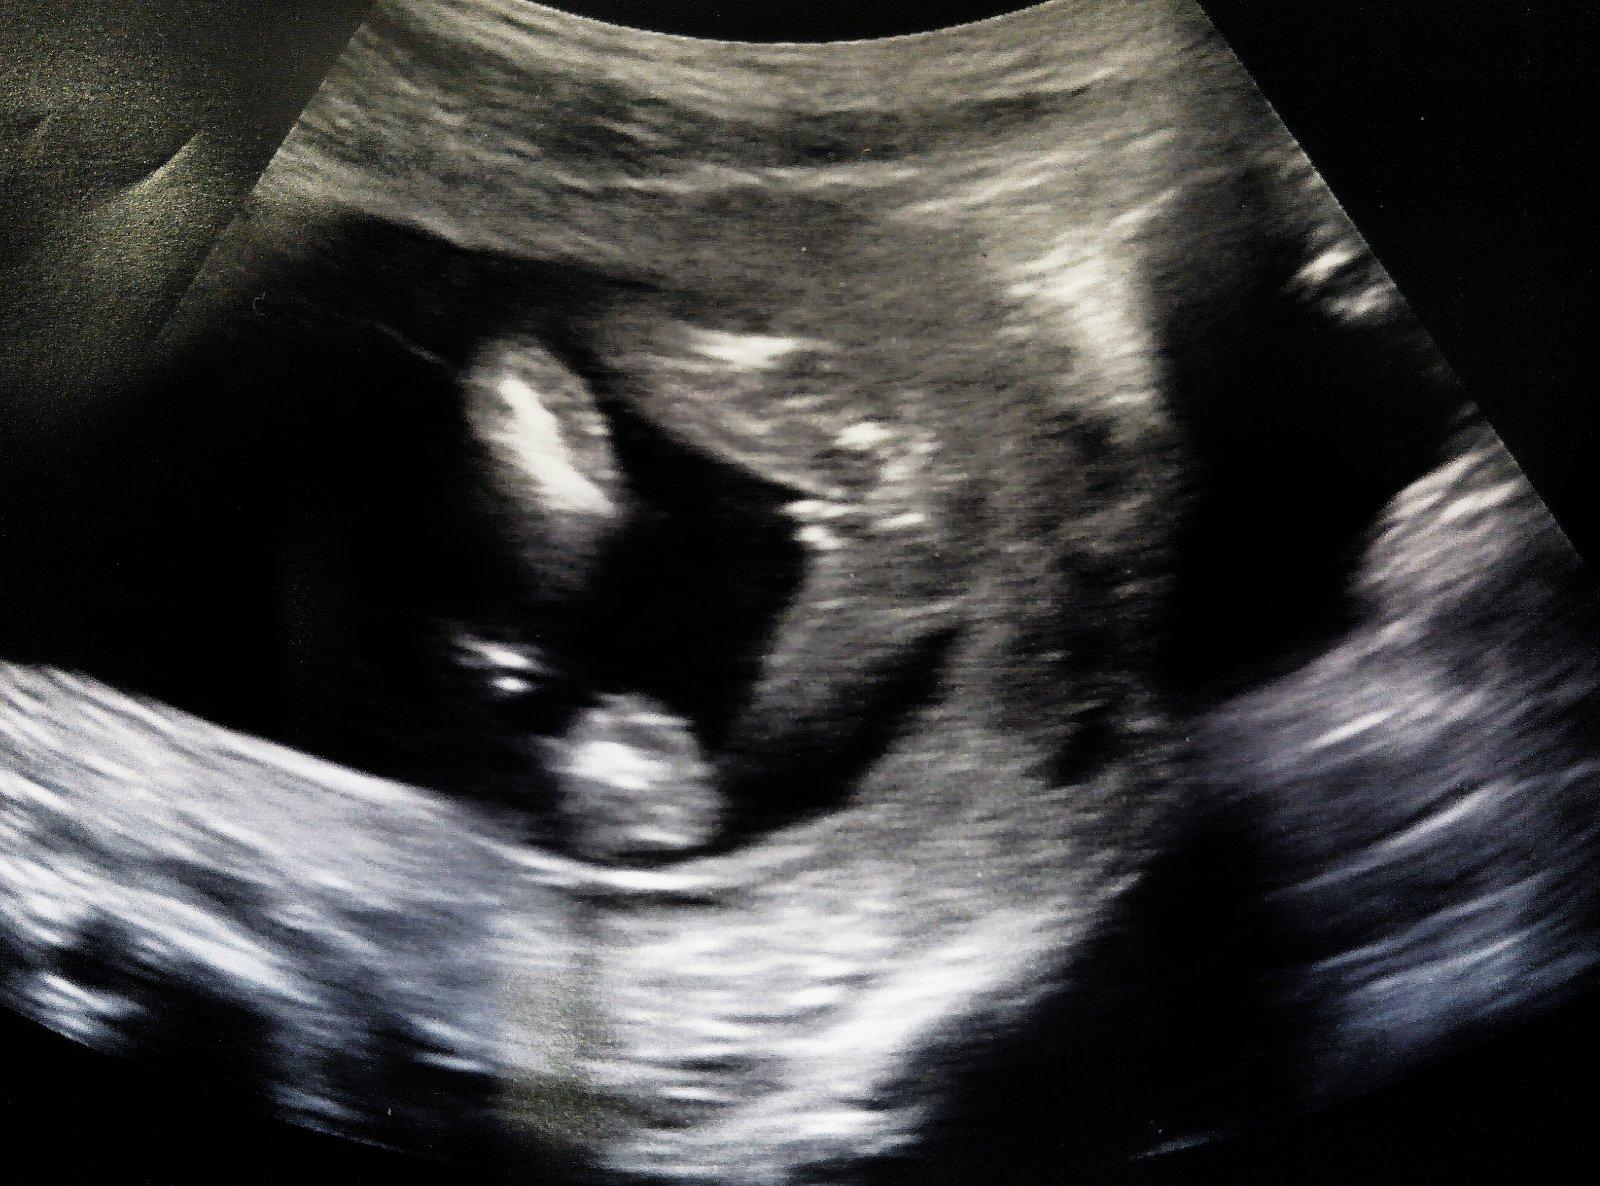

Děkuju moc,máme doma chlapečka,chtěli bychom holčičku,necháme se překvapit 😊

Díky holky 😀 tak dobře, no 😀

@sardelka15 chlapecek? ja myslela, ze ti rikali holcicku 🙂